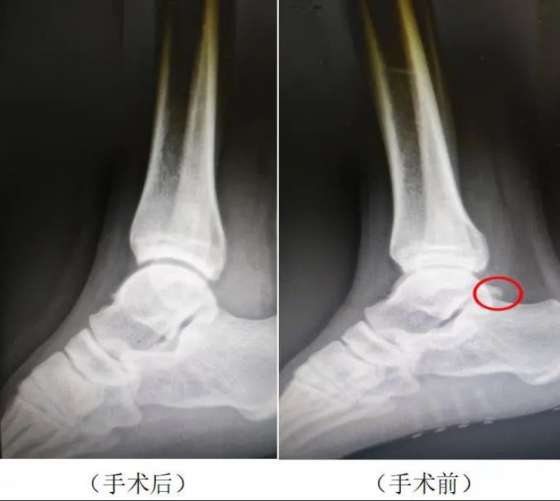

大約8個月前,國(guó)安隊球員闫雨開(kāi)始出現右足跟後(hòu)方疼痛、踝關節跖屈位加重,無法正常發(fā)力起(qǐ)跳,經(jīng)過(guò)休息腫脹有所緩解,但運動後(hòu)依然疼痛,反反複複,導緻無法完成(chéng)日常訓練。爲了徹底解決這(zhè)一健康問題,北京國(guó)安決定由德爾康尼爲闫雨進(jìn)行診斷和治療。經(jīng)影像學(xué)檢查,闫雨被(bèi)初步診斷爲右踝關節撞擊綜合症、右跟距關節後(hòu)方骨贅形成(chéng)、右側跟腱炎。

11月14日,北京德爾康尼骨科醫院副主任醫師邢朝輝醫生爲闫雨實施了關節鏡下右踝關節撞擊綜合症、跟距關節後(hòu)方骨贅切除手術。手術非常成(chéng)功,闫雨目前恢複良好(hǎo),他表示德爾康尼長(cháng)期爲國(guó)家隊高水平運動員進(jìn)行醫療保障服務的寶貴經(jīng)驗和良好(hǎo)的業内聲譽讓他對(duì)手術和康複充滿信心,他也期待不久的將(jiāng)來就能(néng)回到賽場繼續爲球隊貢獻自己的力量。